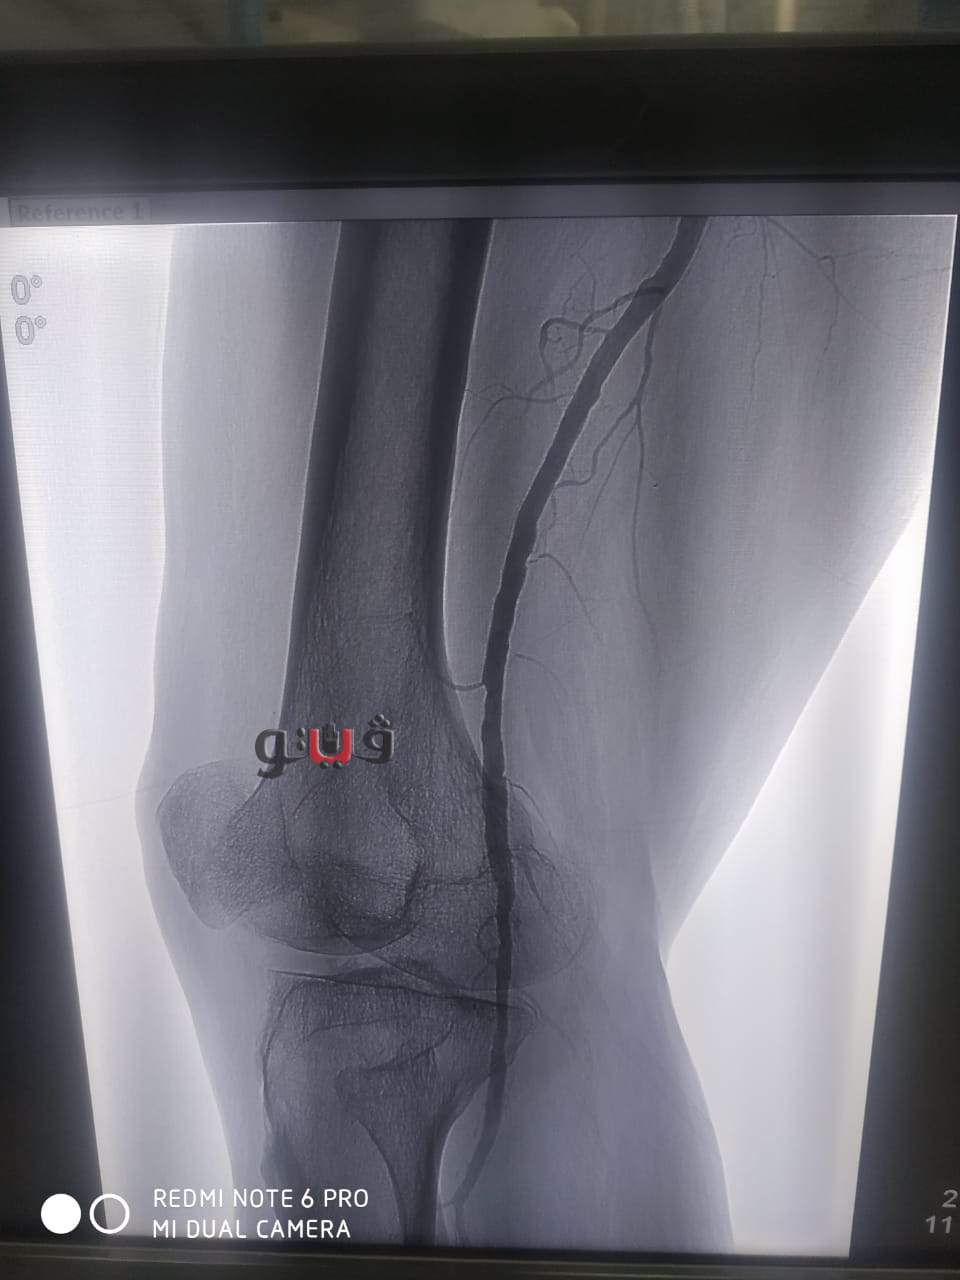

نجاح عملية توسيع بالوني بالقسطرة الطرفية لمريض بمستشفى المنصورة الدولي

شهد مستشفي المنصورة الدولي بمخافظة الدقهلية نجاح فريق طبي بإجراء عملية توسيع بالوني لمريض يبلغ من العمر 65عاما يعاني من قصور دموي حرج بالساق اليمنى.

وأوضح مكي انه تم التدخل الطبي السريع عن طريق القسطرة الطرفية داخل وحدة القسطرة التداخلية بمستشفى المنصورة العام الجديد (الدولي) وتم استعادة وتقوية الدورة الدموية للساق بنجاح عن طريق فريق طبي من قسم جراحة الاوعية الدموية بالمستشفى حيث تمت العملية بنجاح باهر وخرج المريض من العمليات بحالة مستقرة.